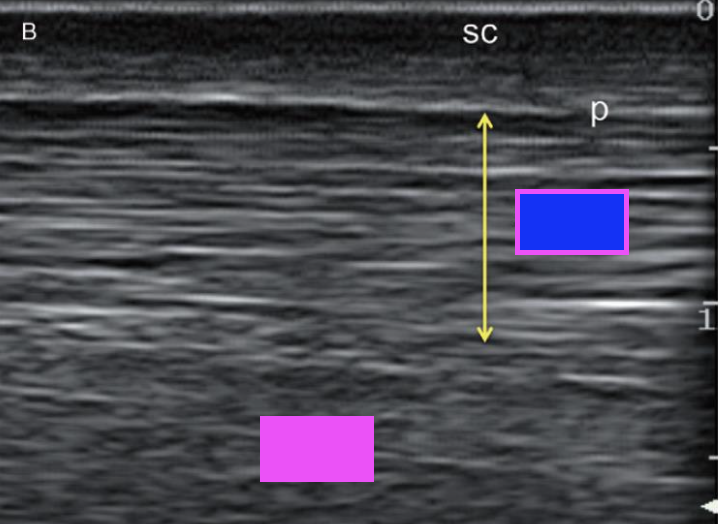

what structure is indicated by the yellow arrows?

superficial digital flexor tendon

what type of ultrasound scan does this show?

longitudinal scan